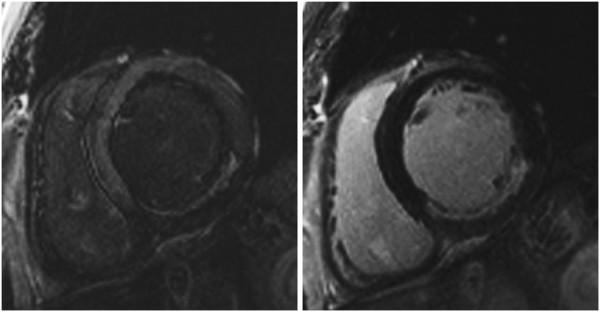

Standardized image interpretation and post processing in cardiovascular magnetic resonance: Society for Cardiovascular Magnetic Resonance (SCMR) board of trustees task force on standardized post processing.

With mounting data on its accuracy and prognostic value, cardiovascular magnetic resonance (CMR) is becoming an increasingly important diagnostic tool with growing utility in clinical routine. Given its versatility and wide range of quantitative parameters, however, agreement on specific standards for the interpretation and post-processing of CMR studies is required to ensure consistent quality and reproducibility of CMR reports. This document addresses this need by providing consensus recommendations developed by the Task Force for Post Processing of the Society for Cardiovascular MR (SCMR). The aim of the task force is to recommend requirements and standards for image interpretation and post processing enabling qualitative and quantitative evaluation of CMR images. Furthermore, pitfalls of CMR image analysis are discussed where appropriate.